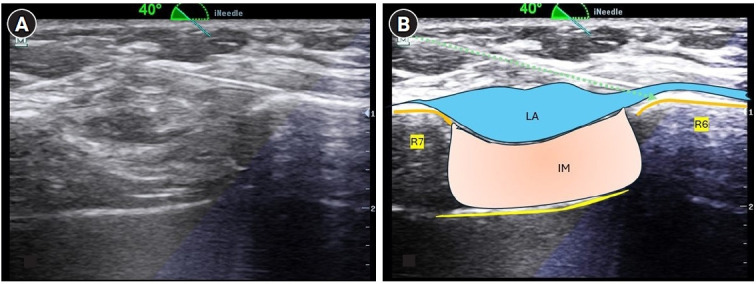

Background: Conventional fascial plane block approaches for upper abdominal surgeries spare the lateral cutaneous nerve. An external oblique intercostal block (EOIB) may be suitable for upper abdominal incisions as it blocks the lateral and anterior branches of the intercostal nerves T6-T10. However, there is a paucity of studies evaluating this block in clinical settings. The study aimed to compare the analgesic efficacy of combined EOIB and rectus sheath block with local infiltration analgesia (LIA) in laparoscopic cholecystectomy (LC).

Methods: After obtaining written informed consent, 70 patients were randomly allocated to undergo right-sided EOIB with 20 ml and left-sided RSB with 10 ml of 0.25% bupivacaine at the end of surgery (group ER, n = 35). Patients in the LIA group (n = 35) underwent local infiltration at the port site using 20 ml of the same solution (group LIA, n=35).